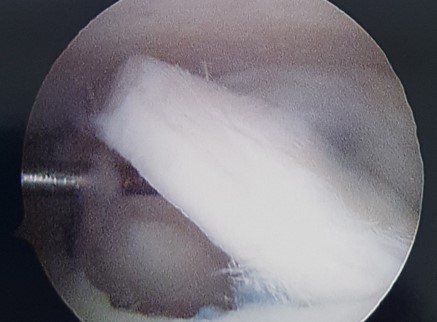

See X-ray and arthroscopic images below.

- ankle arthroscopy.

Surgery involves ankle arthroscopy and cartilage treatment. Depending on the size and depth of cartilage damage, options include:

- cartilage debridement and micro-fracture (+/- application of hydrogel bioscaffold) to stimulate healing (see images below)